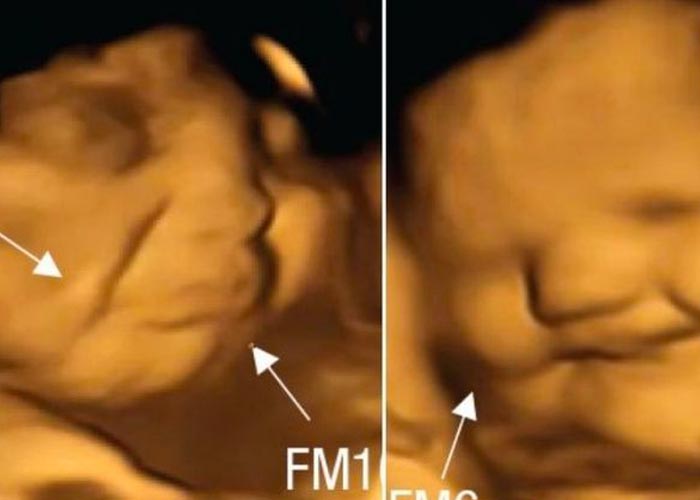

Estas imágenes han permitido observar la forma en la que los futuros bebés reaccionan cuando su madre come zanahoria o col rizada. Ante la zanahoria, los fetos mostraron una «cara riendo«; mientras que los que cuya madre había comido col, tenían una «cara llorosa»; afirmaron los científicos.

Fotos de fetos que reacciona según lo que coma mamá